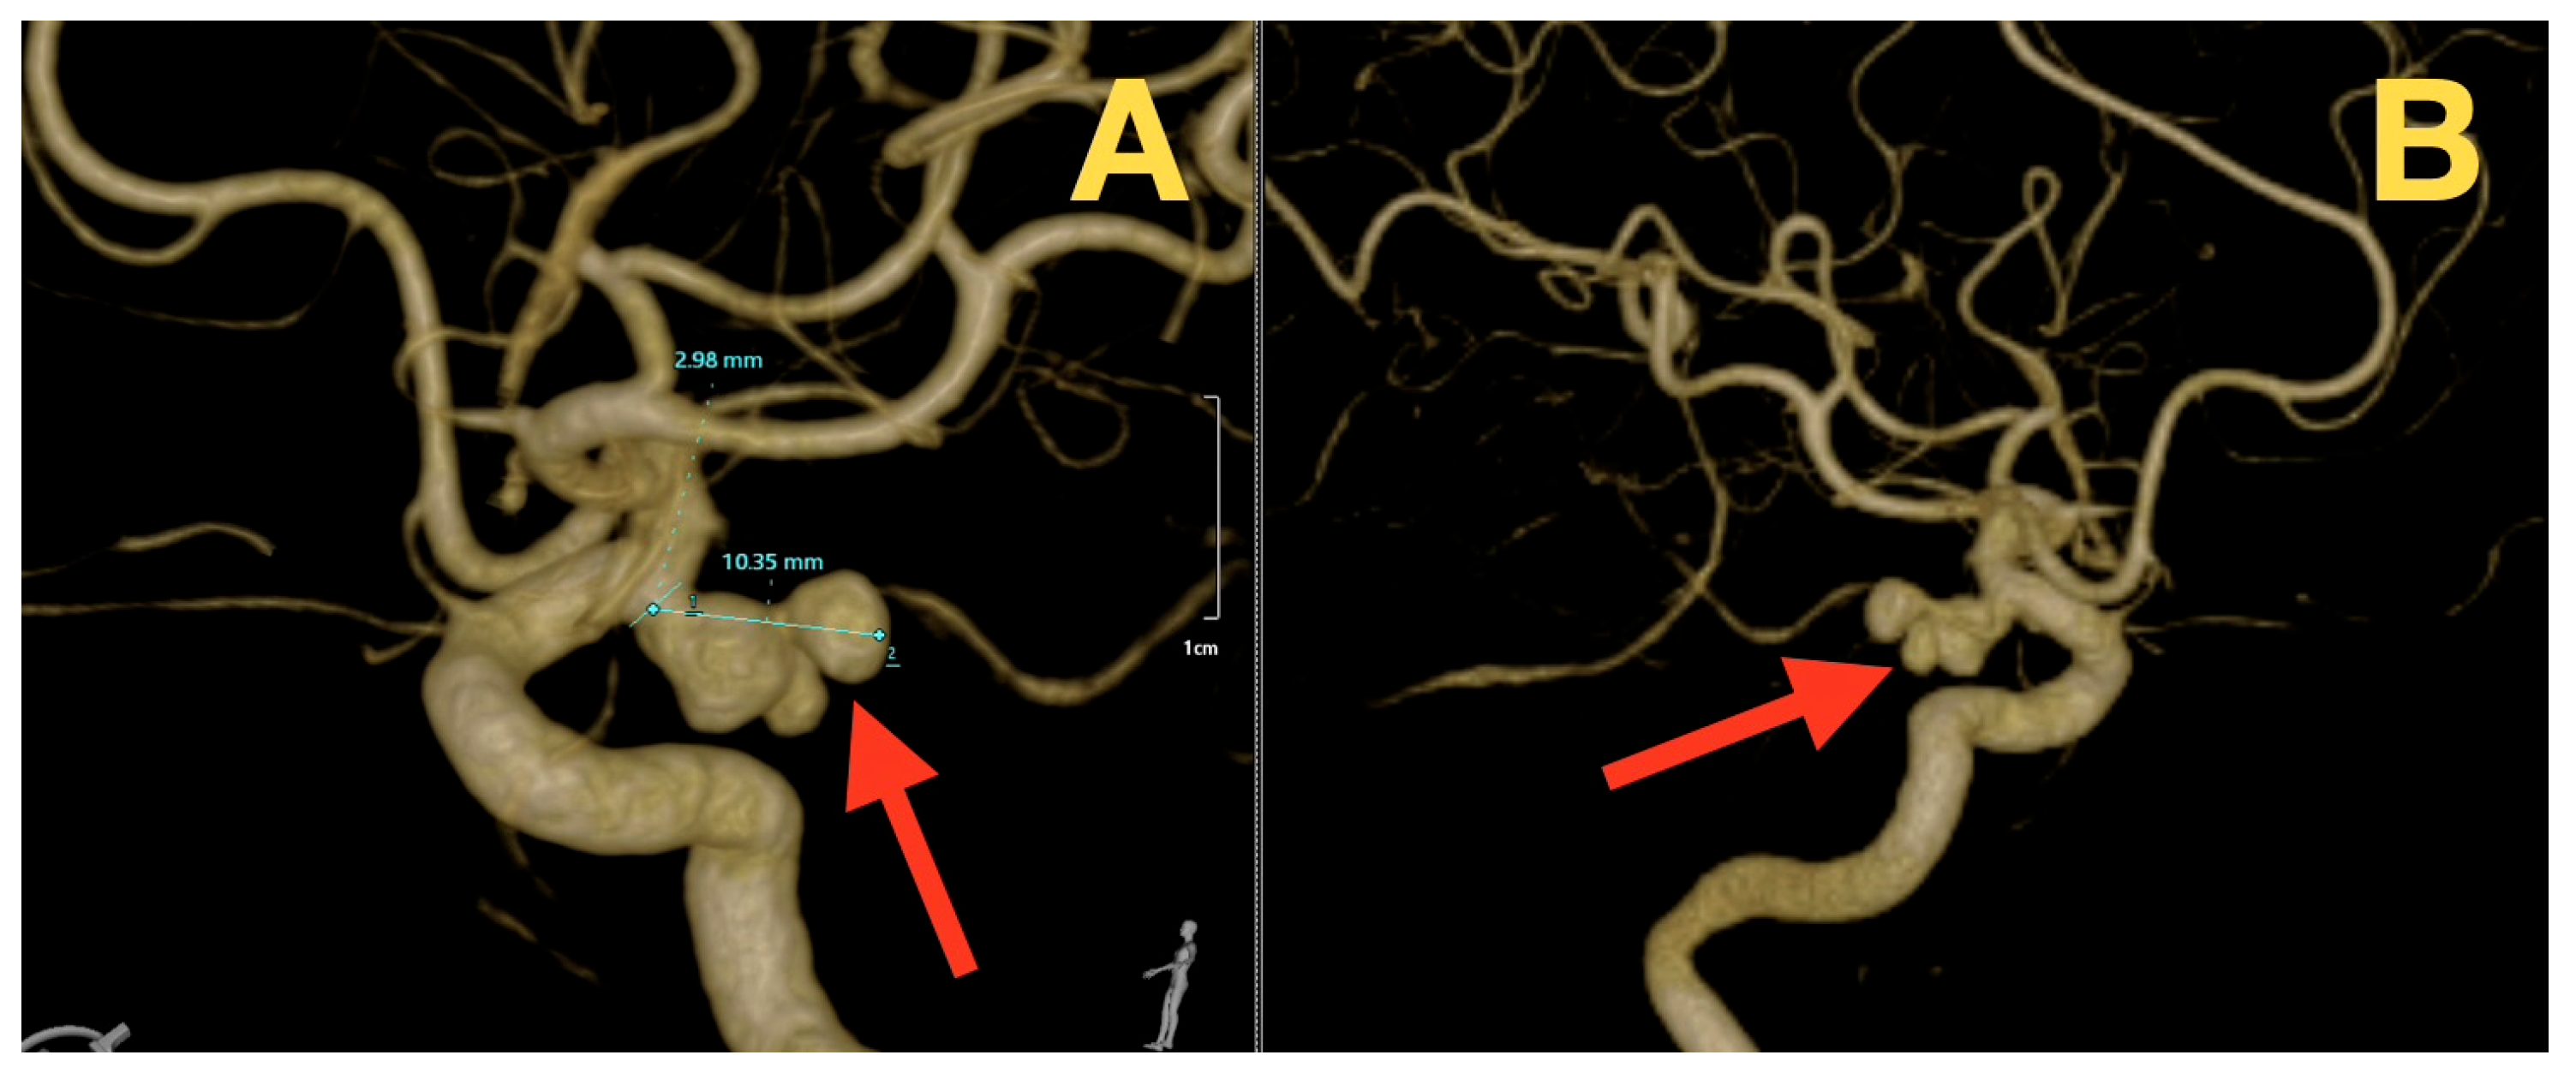

A Ruptured Tri-Lobulated ICA–PCom Aneurysm Presenting with Preserved Neurological Function: Case Report and Clinical–Anatomical Analysis

2. Case Presentation